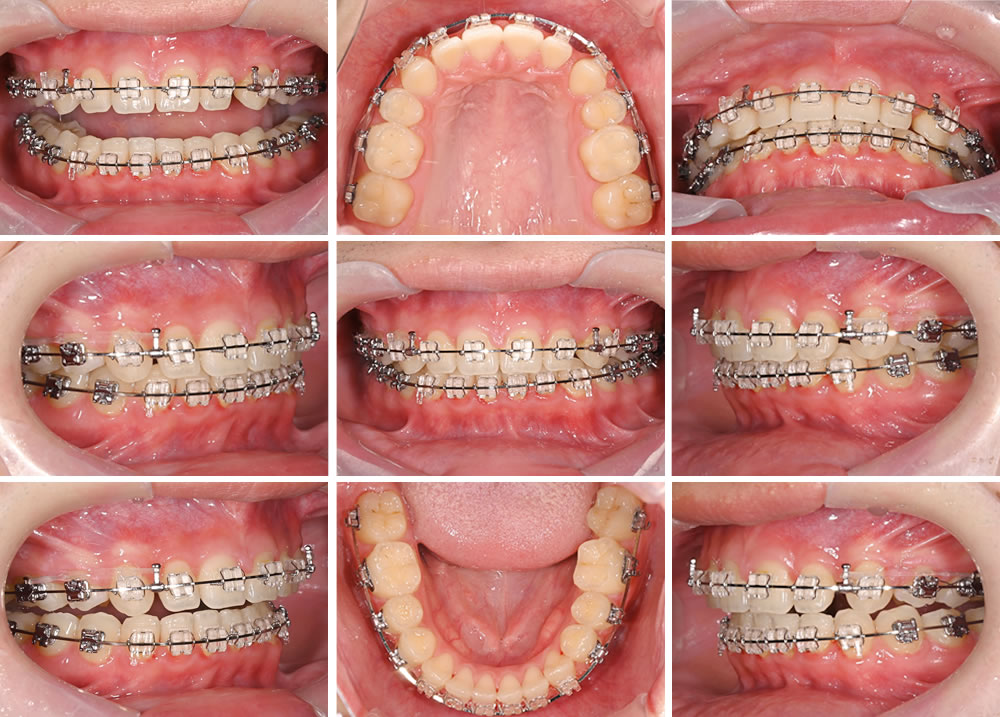

歯がある程度きれいに並んできたら、最終の微調節と噛み合わせを作っていきます。